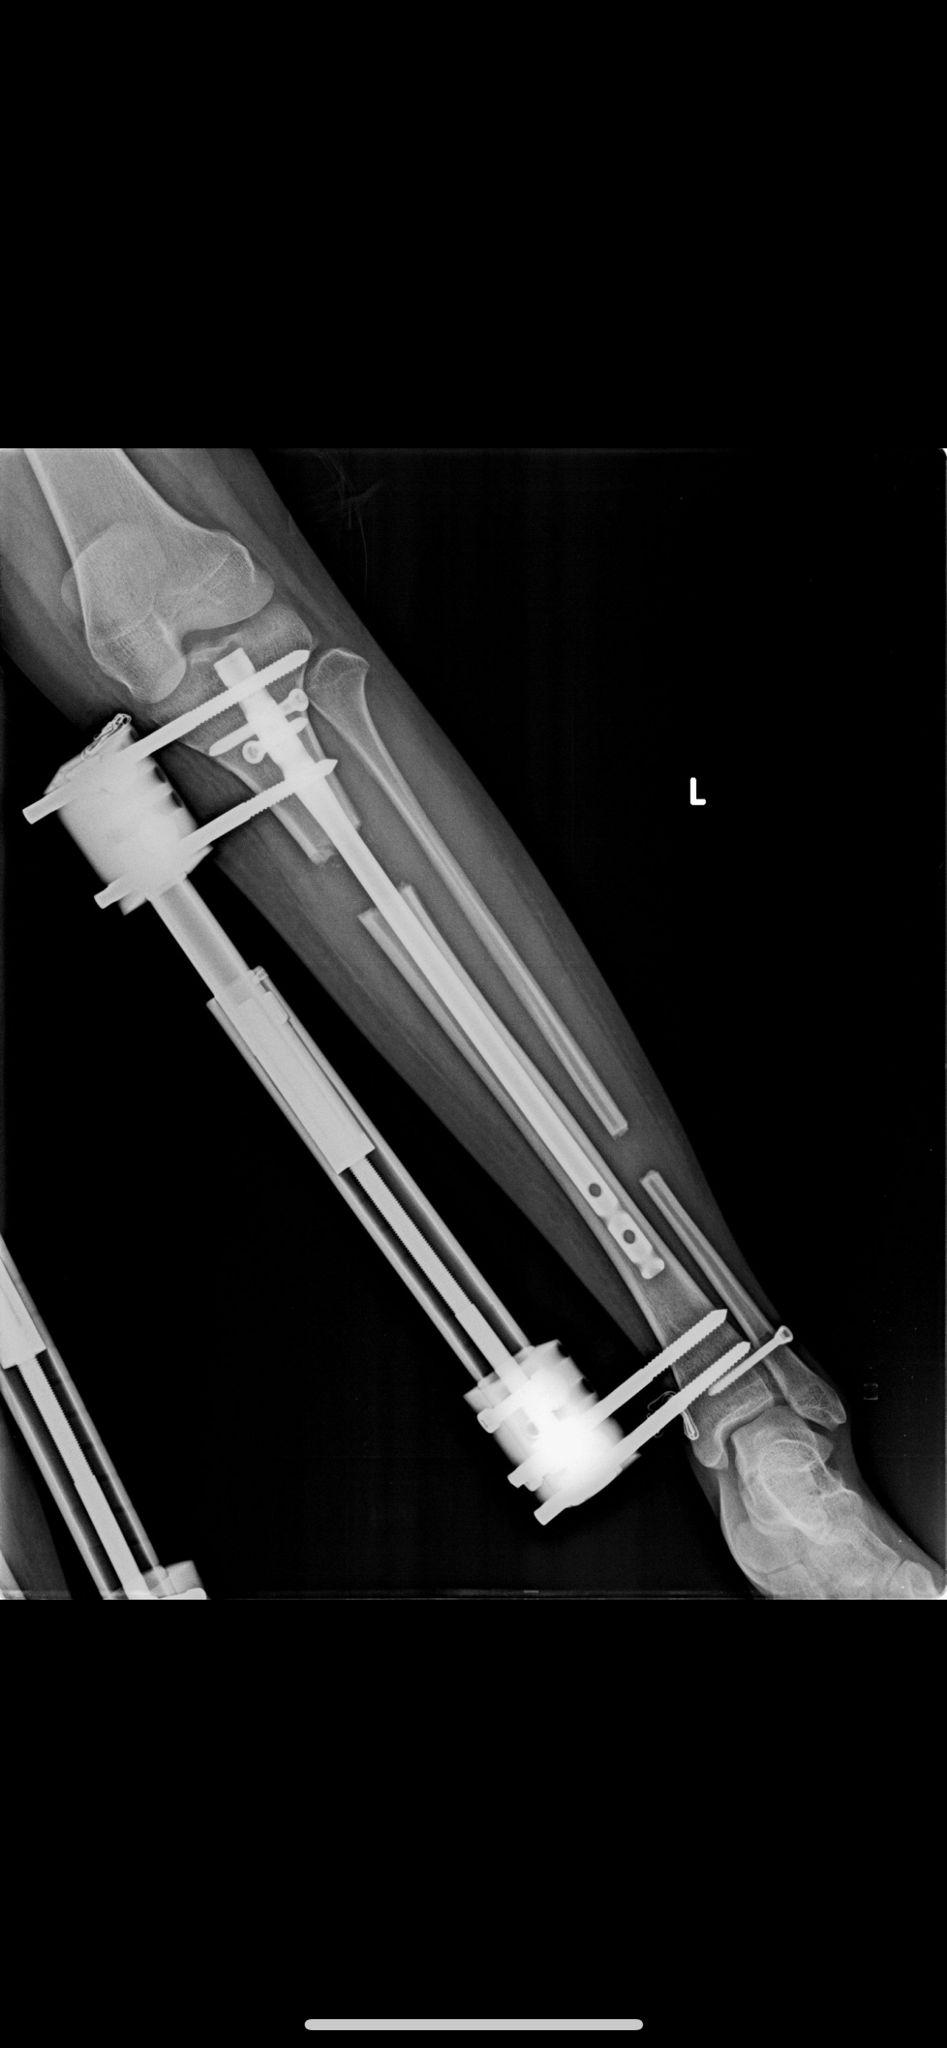

Yöntem ve Röntgen Görüntülerimiz

BAŞARILI SONUÇLARIMIZ

Boy uzatma ameliyatlarımızda kullandığımız modern yöntemlerin röntgen görüntüleri ve başarılı sonuçlarımızı inceleyebilirsiniz.

Fitbone Yöntemi

Fitbone® Yöntemi ile Boy Uzatma Tamamen İçten (Internal) Motorize Uzuv Uzatma Teknolojisi